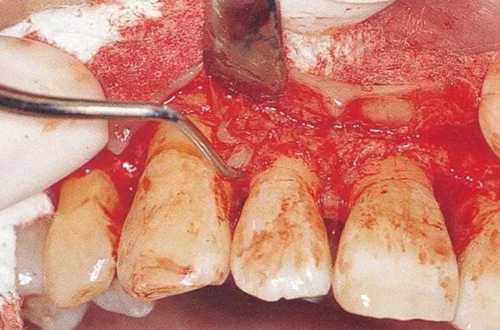

肉芽組織去除后,接下來將牙根表面附著的牙結(jié)石和污染物質(zhì)去除。齦下刮治和根面平整是最重要的一部分。必須要有充分的時間將根面徹底清創(chuàng)。

肉芽組織去除后,出血就可以得到控制,殘存牙結(jié)石的附著狀態(tài)可以更清楚,骨吸收狀態(tài)和骨缺損狀態(tài)的有無也能夠明確知道。另外,術(shù)后治愈效果也會良好。清除牙結(jié)石時,注意不要有殘留(圖15-1~3)。

▼圖15-2(左)  不良肉芽組織去除后出血變少

▼圖15-3(右)  在進行牙冠形成的牙齒上,可以用牙周外科用車針進行SC/RP,手術(shù)時間得以大幅縮短。

19.jpg